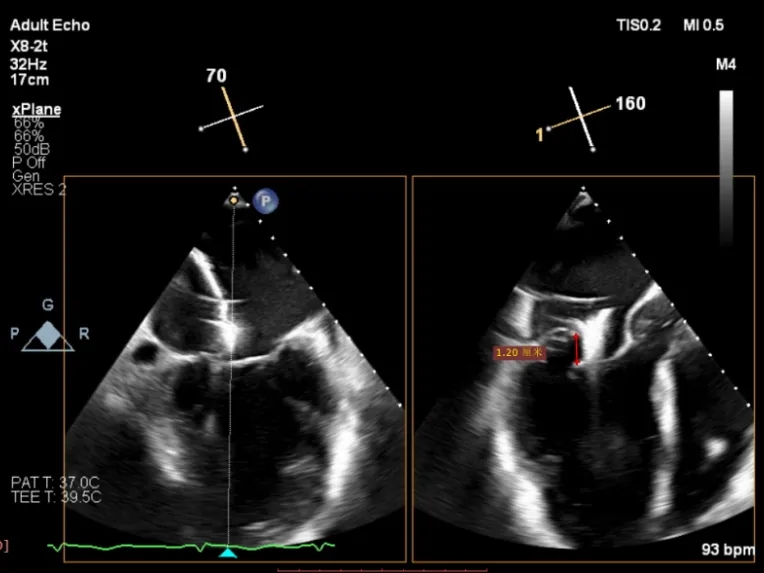

为了避免长时间TEE对食道造成损伤,术前即刻3D-TEE短时进一步明确二尖瓣病变相关解剖情况。

术前Bi-com

3D-TEE二尖瓣相关解剖学参数:后叶长度:22-25mm,前叶长度:31-34mm;瓣环AP径:47mm,ML径:48mm;瓣口面积:约7.8cm²;脱垂宽度:30mm,最大连枷间距:14mm。

四条肺静脉均可测及收缩期反向血流

术前即刻TEE进一步明确了二尖瓣反流的机制(DMR)及反流程度(5+),重点完善了病变区域二尖瓣解剖结构的评估,预估手术难点/影响手术效果的解剖结构为冗长的二尖瓣后叶(PML约25mm),宽大的脱垂(Flail Width约30mm),超大的连枷间距(Flail gap约14mm)。